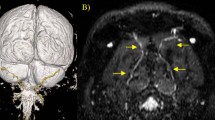

On an ultrasound image taken at the level of the axial spinous process, the position of GON corresponded with that observed in our study (Fig. 4). The nerve was situated between OCI and SSC.

The position of greater occipital nerve (GON) and third occipital nerve (3ON) in cadaveric observation (left illustration) and the corresponding ultrasound images (right images). Upper red line runs through the emergence of GON from the trapezius (TP) and lower one through the spinous process of the axis (C2). Each ultrasound images and their illustrations corresponds to sections through upper and lower red lines respectively. sternocleidomastoid muscle, SCM; splenius capitis, SpC; semispinalis capitis, SSC; obliquus capitis inferior, OCI.